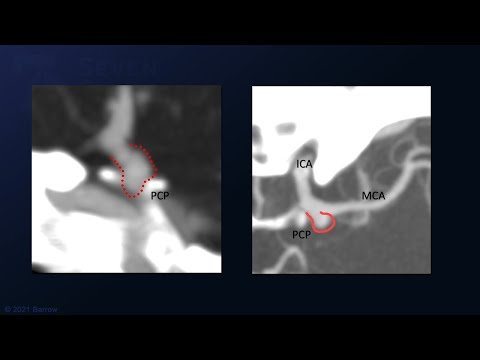

Hellow guys, Welcome to my website, and you are watching PCOMA ANEURYSM. and this vIdeo is uploaded by Dhaval Shukla at 2011-10-04T08:10:16-07:00. We are pramote this video only for entertainment and educational perpose only. So, I hop you like our website.